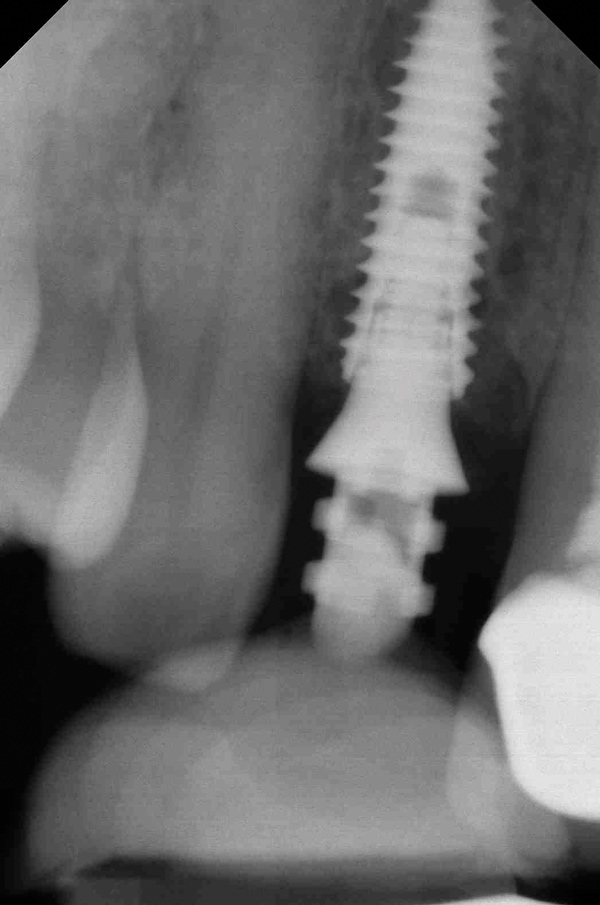

Fig 4. Radiograph showing root fracture and apical lesion of the tooth (No. 7).

Figure 4

Fig 6. Implant was placed in an ideal 3-dimensional position.

Figure 6

Fig 7. Human bone allograft was placed in the gap.

Figure 7

Fig 10. Periapical radiograph showing implant placement with abutment in place for fabrication of provisional crown.

Figure 10